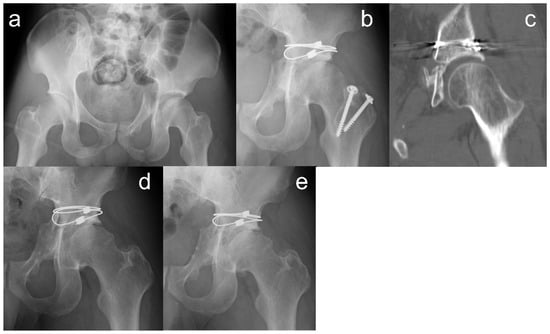

| 1 | 38 | M | 18.1 | Snowboard | 9 | 11 | BC + PW | − | 209 | 309 | Anatomical | Tönnis II | 93 | 84 |

| 2 | 44 | M | 15.3 | TA | 10 | 17 | TV | − | 190 | 482 | Anatomical | − | 99 | 93 |

| 3 | 64 | M | 15.0 | Fall | 18 | 15 | BC | − | 155 | 574 | Imperfect | Tönnis I | 79 | 98 |

| 4 | 28 | M | 16.3 | Fall | 18 | 27 | BC | − | 330 | 1941 | Poor | Tönnis I | 87 | 91 |

| 5 | 39 | M | 14.6 | Fall | 22 | 11 | BC | + | 186 | 596 | Anatomical | − | 91 | 100 |

| 6 | 34 | M | 14.5 | Fall | 9 | 6 | TV | + | 222 | 801 | Imperfect | − | 93 | 93 |

| 7 | 61 | F | 10.9 | TA | 14 | 22 | TS | − | 194 | 800 | Anatomical | − | 85 | 90 |

| 8 | 74 | F | 11.2 | TA | 11 | 8 | TV + PW | + | 163 | 281 | Imperfect | Tönnis III | 71 | 74 |

| 9 | 42 | M | 10.8 | TA | 11 | 8 | TS | − | 143 | 220 | Anatomical | − | 95 | 95 |